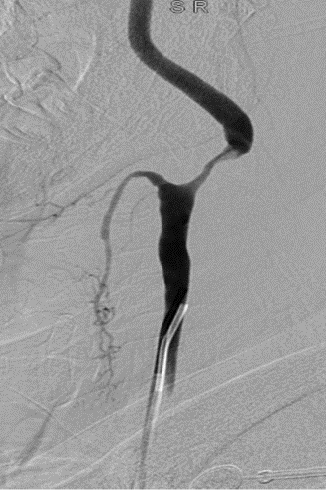

Wallstent 7-40mm颈动脉支架支架置入。

波科支架怎么样径技-弓上病例大赏|第205期·放疗后症状性颈动脉狭窄支架置入治疗一例_https://www.jmylbn.com_新闻资讯_第17张

波科支架怎么样径技-弓上病例大赏|第205期·放疗后症状性颈动脉狭窄支架置入治疗一例_https://www.jmylbn.com_新闻资讯_第18张

波科支架怎么样径技-弓上病例大赏|第205期·放疗后症状性颈动脉狭窄支架置入治疗一例_https://www.jmylbn.com_新闻资讯_第19张

➢ 本例患者应用的波科保护伞(FilterWire EZ3.5mm-5.5mm)具有高捕获率及可靠的贴壁性能同时有良好的输送性,不用微导丝导引,操作过程中内膜损伤及产生夹层风险小并且回收简单。该患者术后保护伞回收后可见捕获的脱落斑块

➢ Wallstent颈动脉支架为闭环编织设计,具有高度的柔顺性,贴壁性更好,网眼密,斑块覆盖率高,术中显影好,半释放后仍可回收,便于定位,非常适合本病例血管不稳定斑块及术中夹层病变的血管治疗。